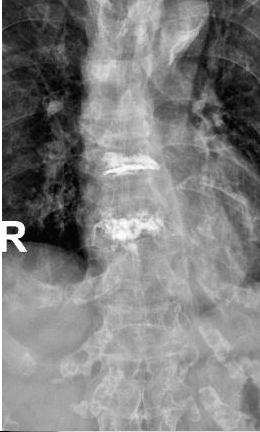

术中,负责人贺毅及团队在C型臂X线透视下,避开神经血管,通过4个3mm的小切口将穿刺针精准抵达骨折部位T9和T11,注入“骨水泥”强化椎体,术中严格控制骨水泥灌注速度与剂量,避免渗漏风险。全程局麻,李奶奶意识清醒,无痛感,出血不足5毫升,术后李奶奶疼痛评分从8分骤降至2分,次日即在支具保护下自主行走,顺利出院。